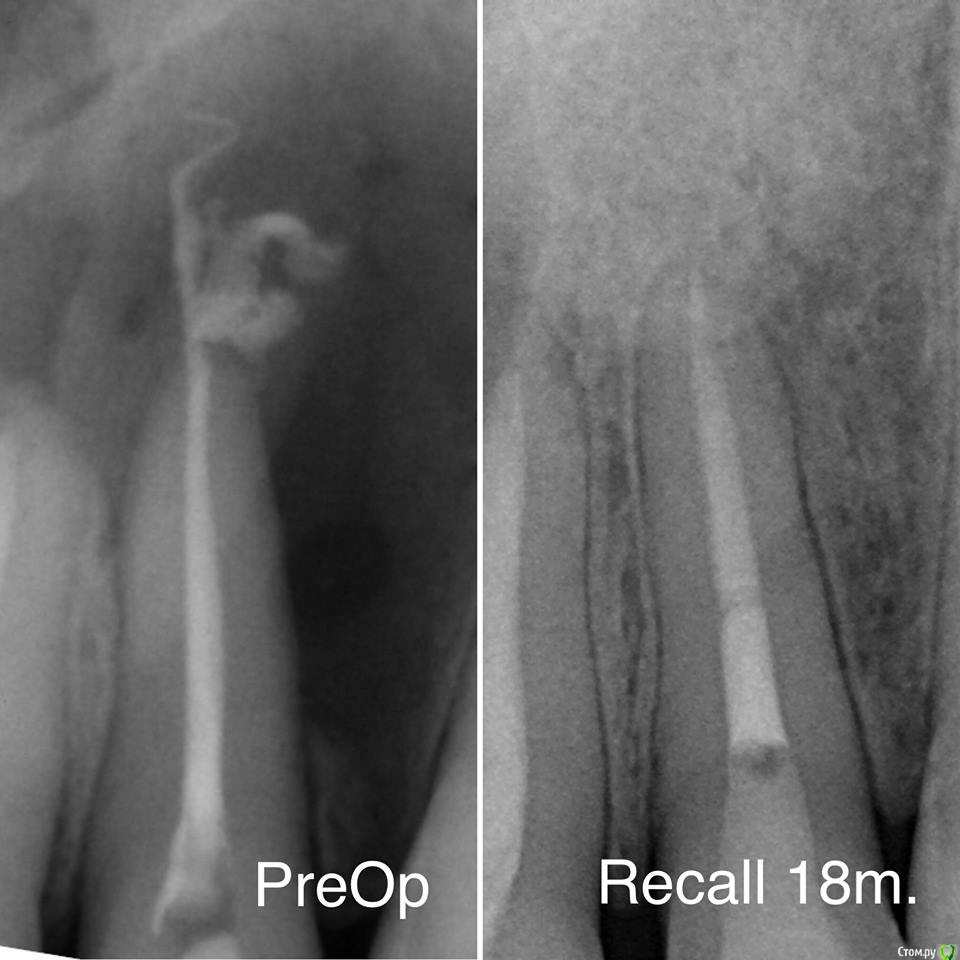

Гарриевич Опубликовано 2 октября, 2018 Автор Поделиться Опубликовано 2 октября, 2018 пришло время отчета 5 Ссылка на комментарий

DmitrySH Опубликовано 3 октября, 2018 Поделиться Опубликовано 3 октября, 2018 Закономерный результат достойной работы! 2 Ссылка на комментарий